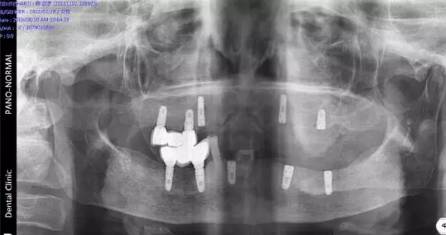

現(xiàn)場北京口腔醫(yī)學(xué)會專家、德國專家親自接診,經(jīng)過口腔CT確診,老人全口牙缺失,為其制定CHEESE德國激光種植技術(shù),8根牙根種出滿口好牙,不僅當(dāng)天種好,還省了錢。

(現(xiàn)場口腔CT拍片)